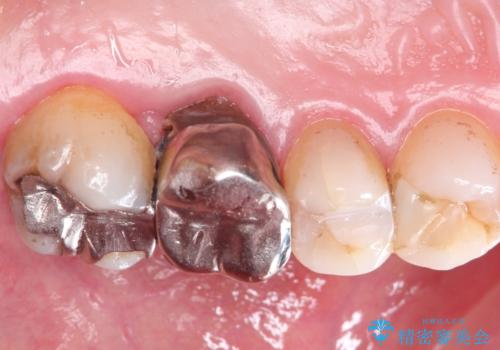

発見の難しい虫歯。根管治療から被せもの治療

- 定期検診にて被せものと歯との隙間に虫歯を発見した患者様です。

根管治療から被せもの治療(ベレッツァ)まで行いました。(根管治療は林院長に依頼)